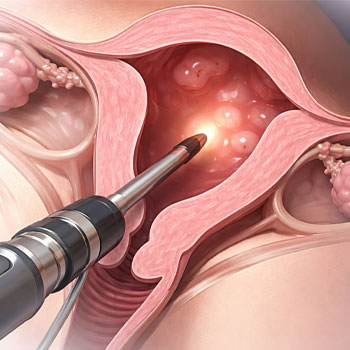

What gynecology services do you offer?

We offer comprehensive women’s healthcare including pregnancy care, menstrual disorder treatment, infertility evaluation, and routine checkups with experienced gynecologists in a supportive environment